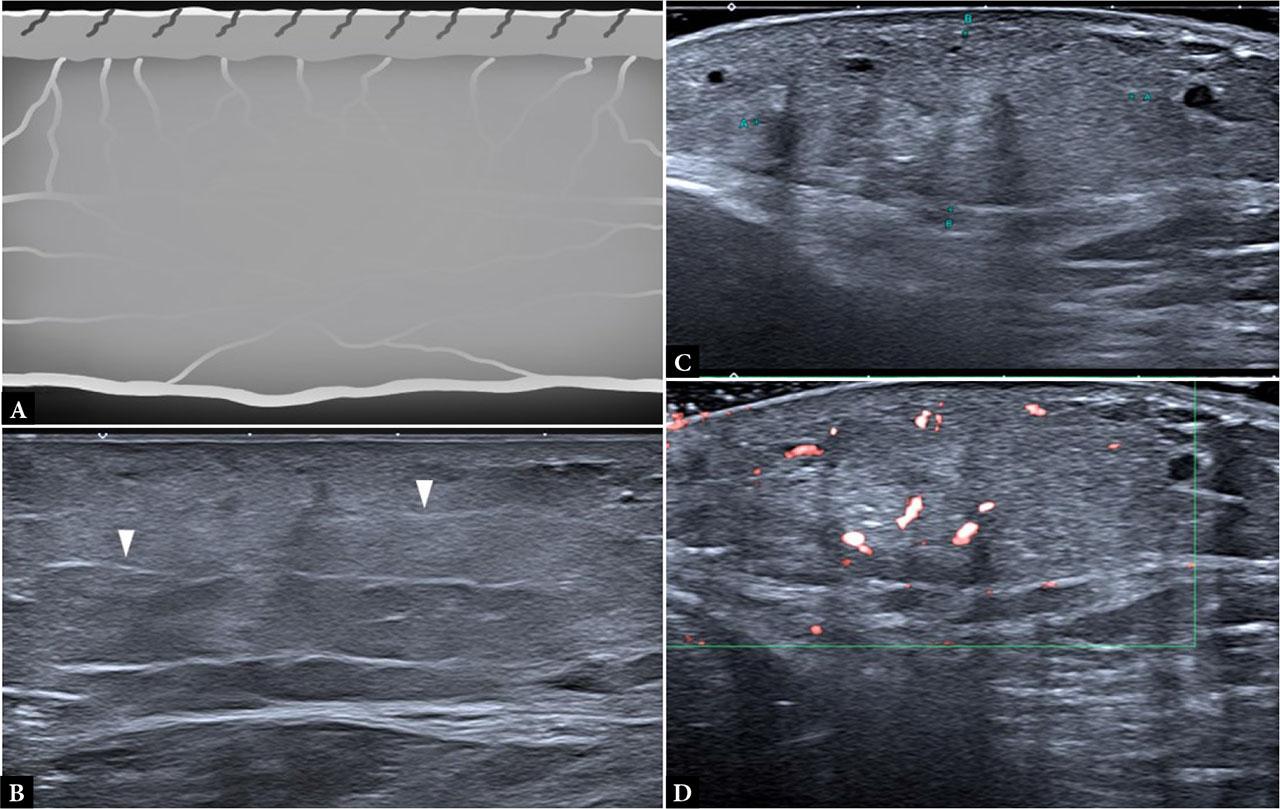

Morphea is an uncommon autoimmune disease that causes inflammation and sclerosis of the skin and subcutaneous tissue. The disease evolves through episodes of activity with inflammation and fibrosis, leading to permanent tissue damage and pigmentary changes. Four major subtypes are recognized: plaque-type (circumscribed), linear, generalized, and mixed. Plaque-type and linear morphea are the most common.

The most sensitive and specific ultrasound markers of disease activity include loss of the dermal-hypodermal interface, increased echogenicity of the subcutaneous tissue, and increased cutaneous blood flow. Another sign is a hypoechoic halo that surrounds subcutaneous venous vessels, called the “sun-sign”(10). In about one-third of cases, there is unsuspected involvement of the underlying muscle and fascia immediately beneath the skin lesion. In the atrophic phase, thinning of the dermis and hypodermis has been described, with increased echogenicity and a fibrillar pattern; however, dermal thickening may persist in many cases (Fig. 5).

Morphea. Inflammatory phase: A. Extended field-of-view image of the lateral aspect of the leg, showing a lobular panniculitis sonographic pattern in the subcutaneous tissue (**) with muscular regional involvement (white arrows); B. Extended field-of-view image showing a mixed panniculitis sonographic pattern involving the entire thickness of the SAT at the lateral aspect of the thigh; C, D. Same case: B-mode and Power Doppler axial sonograms demonstrating a septal panniculitis pattern with septal hyperemia. Sclerotic phase: E. Increased thickness of the hypoechoic dermis (doble arrow) with thinning of the hypodermis and a fibrillar pattern (*); F. Atrophic phase: normal dermis and severe hypodermis thinning; note the absence of fatty lobules (*)

It is strongly recommended to examine the adjacent body regions, since the presence of subclinical disease activity is common.